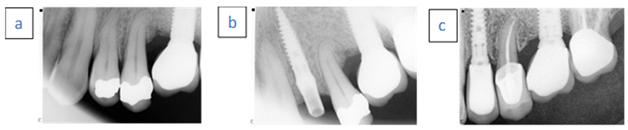

- A 65-year-old female patient.

- Nonsmoker with chronic advanced periodontitis.

- Case 1 (a) A hopeless second right premolar due to vertical root fracture.

- Case 1 (b) Immediate implant placement with temporary abutment.

- Case1 (c) Follow-up examination after 38 months.

- A 56-year-old male patient.

- Case 2 (a) A hopeless left maxillary first premolar tooth due to vertical fracture.

- Case 2 (b) Immediate implant placement with temporary abutment. Radiopaque material demonstrated above the implant neck.

- Case 2 (c) Follow-up examination after 36 months.

- A 46-year-old female.

- Nonsmoker with generalized aggressive periodontitis.

- Case 3 (a) Hopeless left central incisor due to advanced bone loss.

- Case 3 (b) Immediate implant placement with temporary abutment. Radiopaque material demonstrated above the implant neck.

- Case 3 (c) Follow-up examination after 96 months.

- A 76-year-old female.

- Case 4 (a) Hopeless left lateral first incisor due to external root resorption.

- Case 4 (b) Immediate implant placement with temporary abutment.

- Case 4 (c) Follow-up examination after 24 months.